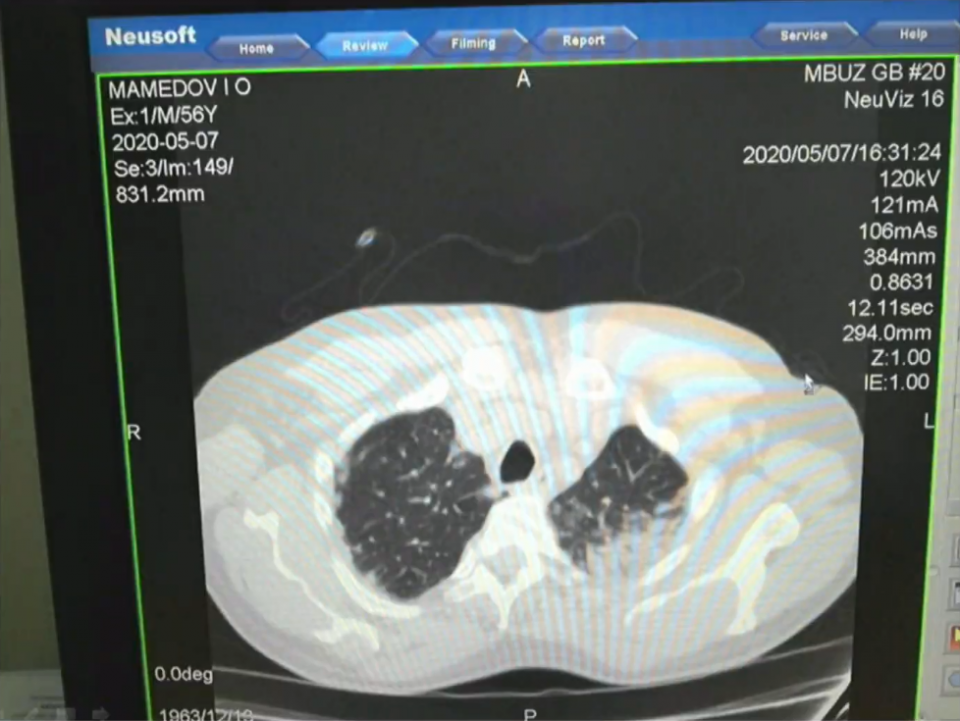

Рентгеновские снимки легких больных коронавирусом в ходе заседания оперштаба показала Татьяна Быковская.

Снимки она продемонстрировала с разрешения пациентов.

— Всё, что темное, — это ткань легкого, а светлое — так называемое матовое стекло. Это показатель того, что наступает необратимый процесс. Легкие наполняются кровью, и дышать пациент самостоятельно не может, — пояснила Быковская.

Причем легкие поражаются с большой скоростью, иногда за несколько часов область поражения увеличивается в несколько раз.